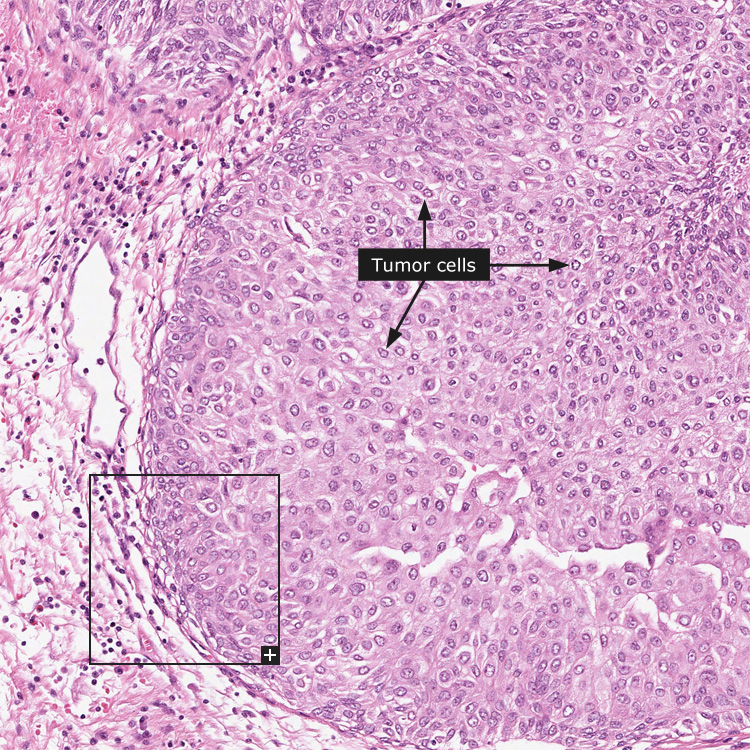

Neoplasms Of The Renal Medulla: Radiologic-Pathologic Correlation

Introduction Neoplasms of the renal medulla constitute a het-erogeneous group of tumors with characteristic histomorphology and variable imaging features. ... Get Document